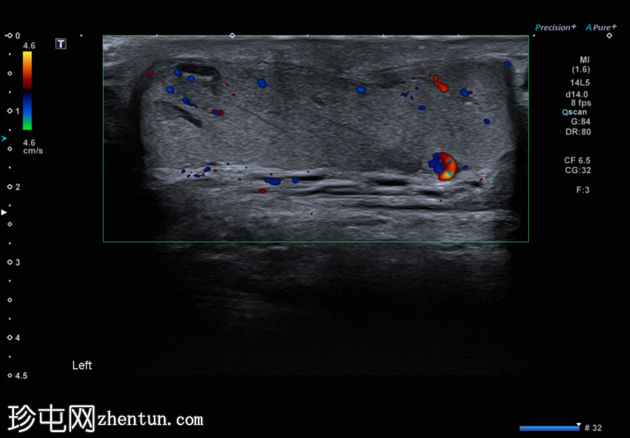

纵切面

左侧睾丸内血管呈迂曲管状扩张,Valsalva动作可见充血。

典型的管状睾丸内精索静脉曲张超声表现,Valsalva动作可见扩张的睾丸内静脉充血。睾丸内精索静脉曲张常与同侧儿童时期睾丸固定术相关,本例患者即曾接受过该手术,且多见于左侧,本例亦属如此。